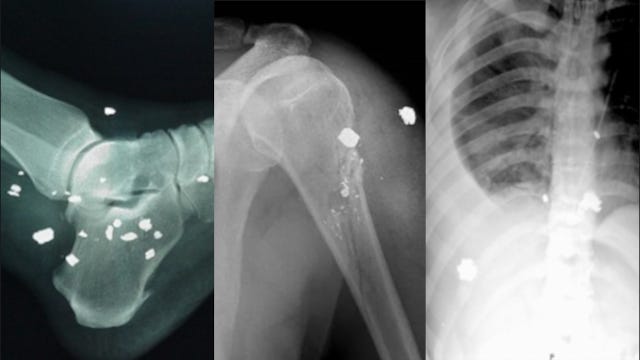

Here are some other images of internal shrapnel with neither "fuzzy outlines" nor black space air pockets. Presumably, Neil Sanders would not consider them real.